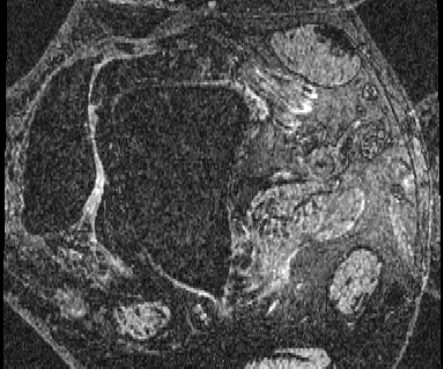

HCP Brain MRI We train on 1076 brain-extracted T1w images from the HCP dataset [24] and test on a sample of 100 pairs between 36 images via mean Dice over 28 midbrain structures [20, 21]. We train and execute the network at [130155130], then compute the Dice score at full resolution.

OASIS Brain MRI We use the OASIS-1 [12] data preprocessed by [9]. This dataset contains images of 414 subjects. Following the data split in [14], we train on 255 images and test on 153 images555Due to changes in the OASIS-1 data, our test set slightly differs from [14]. We evaluate all methods using our testing protocol so that results are consistent.The images in the dataset are of size [160192224], and we crop the center of the image according to the preprocessing in [14], leading to a size of [160144192]. During training, we sample image pairs randomly from the train set. For evaluation, we randomly pick 5 cases as the fixed images and register all the remaining 148 cases to the 5 cases, resulting in 740 image pairs overall.

| Moving Image | Warped Image | Fixed Image | Moving Image | Warped Image | Fixed Image |